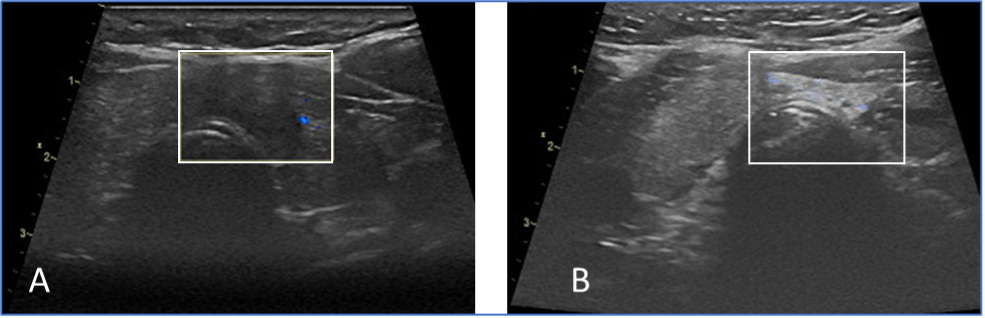

A: Thyroid cancer is within marker. The cancer was destroyed with thermal ablation.

B: After the therapy (6 month) the cancer was completely removed from the body. A small scar develops in the treated area.